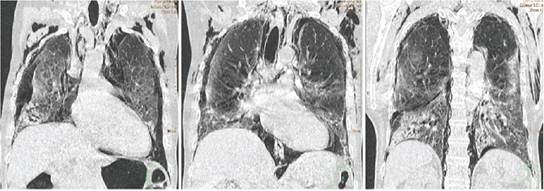

Debido a esto se decide tomografía urgente de control, la cual mostró un neumotórax bilateral de grado moderado asociado a un importante neumomediastino, enfisema subcutáneo en partes blandas de cuello y regiones escapulares, colapso parcial no mayor al 70% de ambos pulmones y la persistencia de infiltrados intersticio-acinares con tendencia a consolidación en bases pulmonares (Ver Figura 1, 2 y 3). Por todo lo anterior se decidió la colocación de sondas torácicas bilaterales inmediatamente. Ante el cuadro progresivo desfavorable que demostró el paciente, se realiza valoración por unidad de cuidados intensivos y durante el traslado al mismo llega a fallecer.